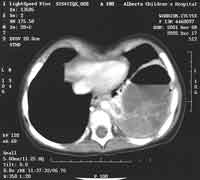

decided to proceed with a CT of the chest in preparation for surgical

drainage of the"abscess". We felt that intra-operative drainage was

the indicated procedure.

ENLARGE the CT scan above

WHAT IS YOUR INTERPRETATION?